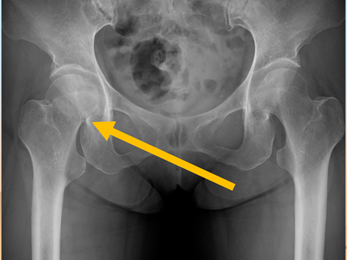

⑤転んだあと、右ひざが痛くて歩いて来院→大腿骨頚部骨折(下図)

⑥右ひざが痛くて歩きづらい→変形性股関節症(下図)